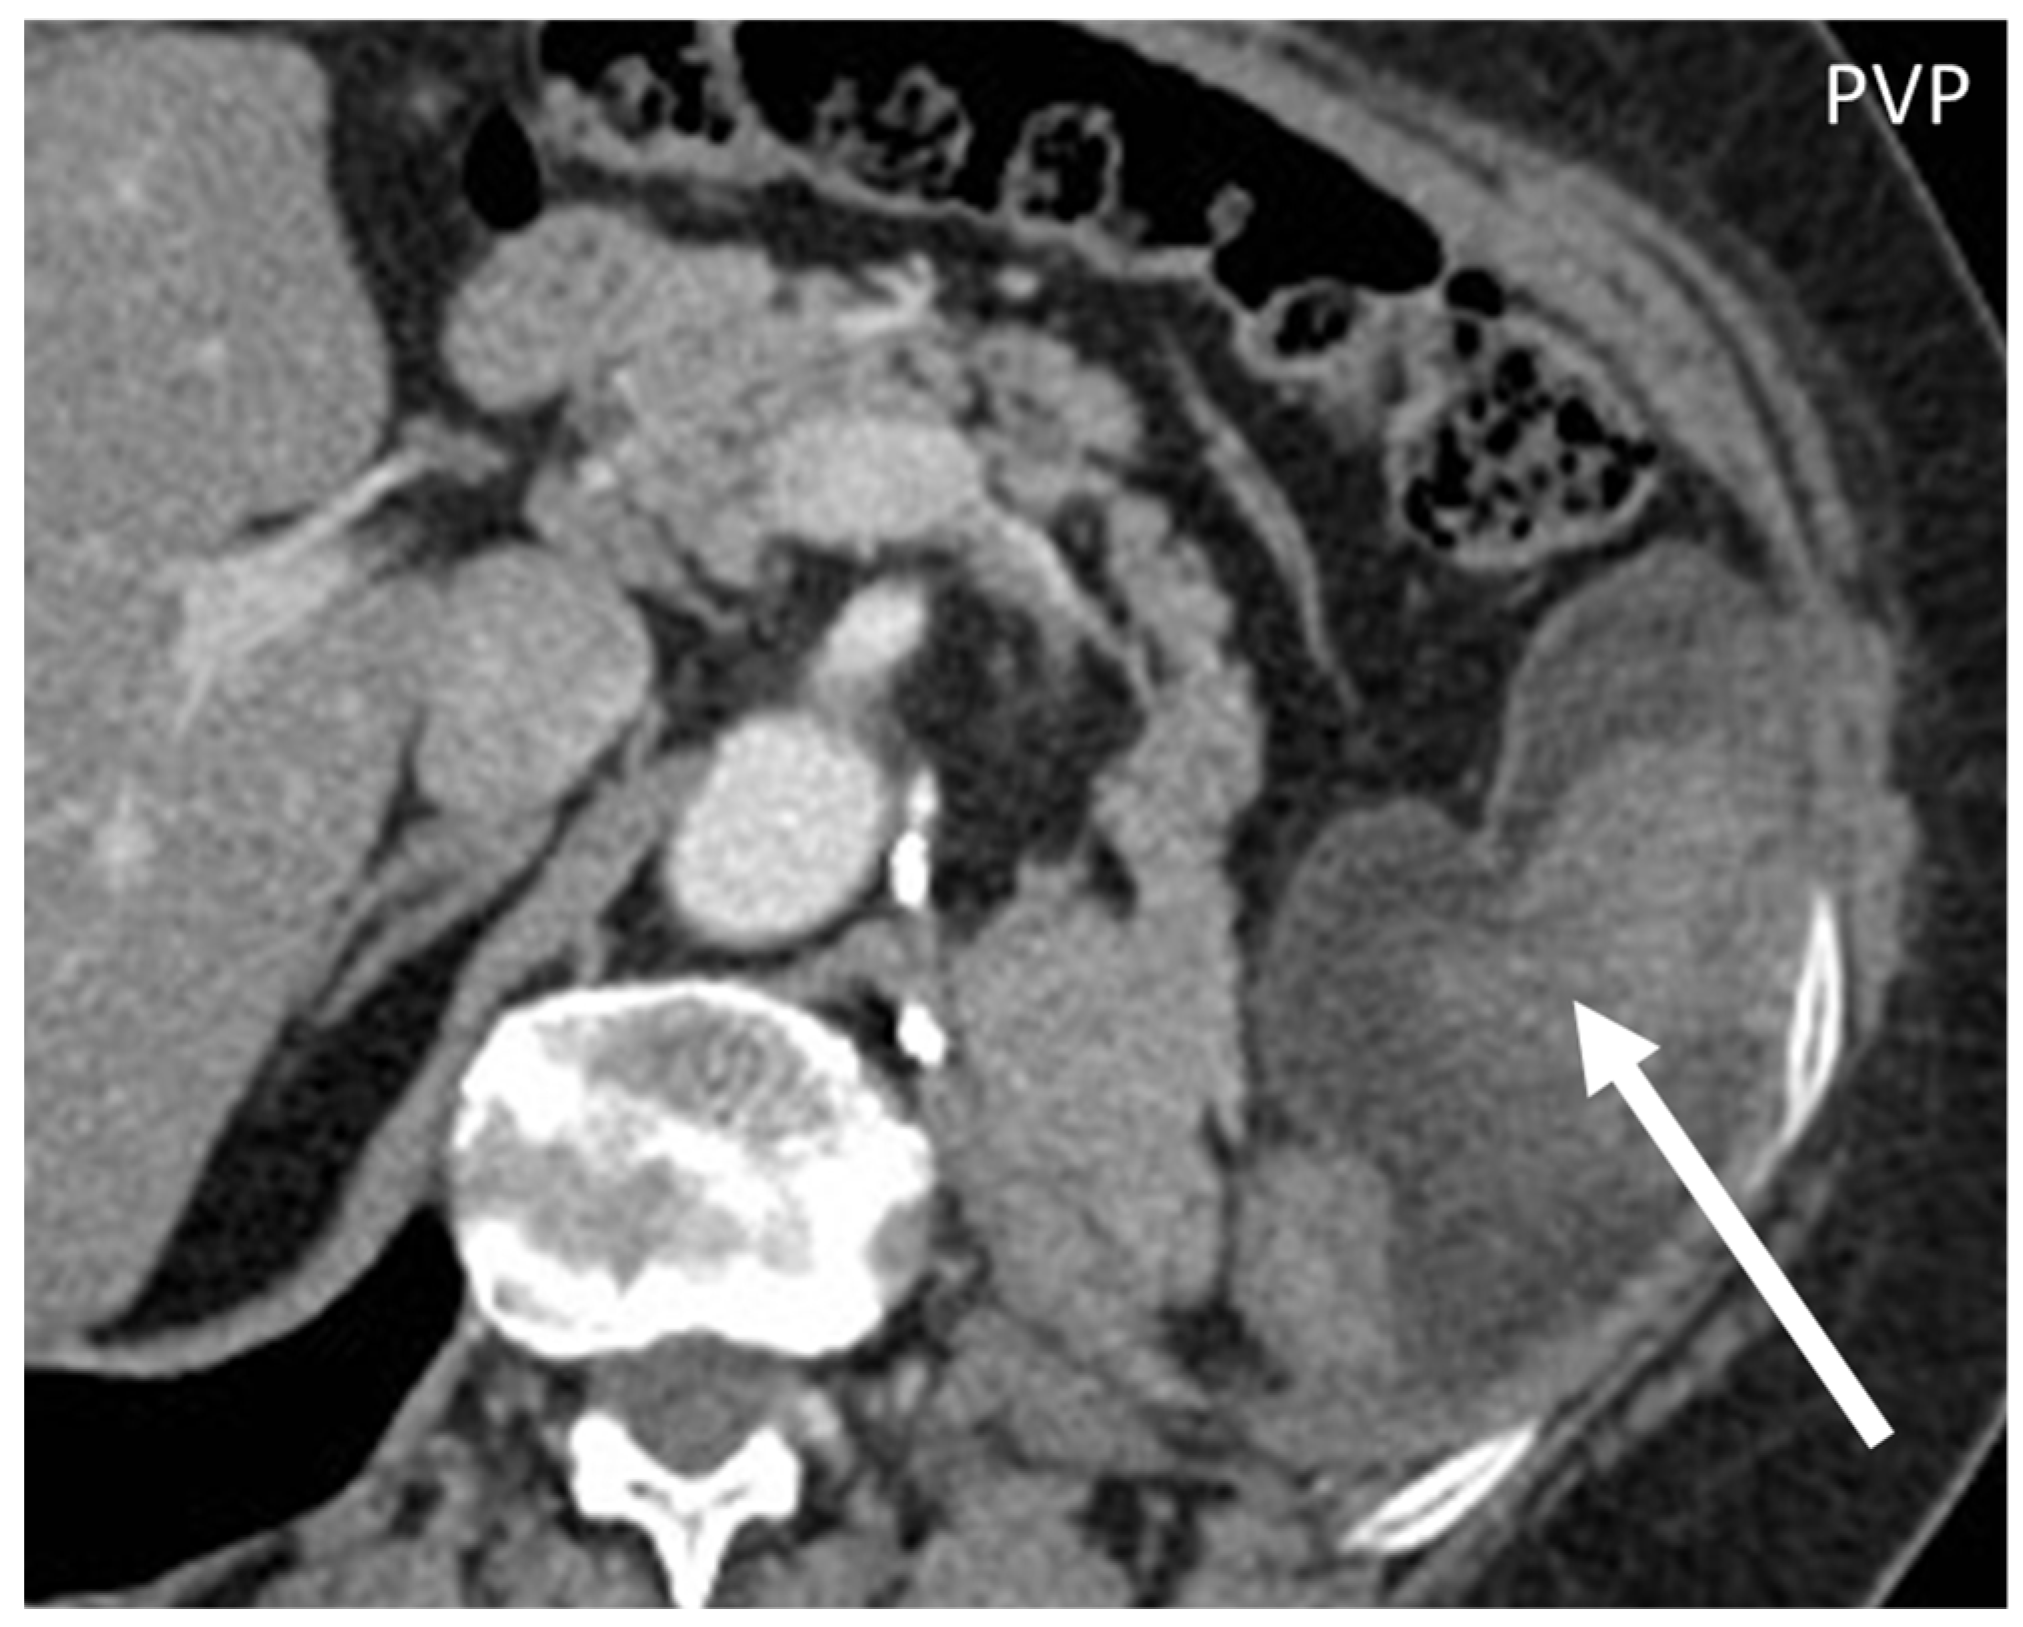

- Leiomyosarcomas: seen on the abdominal wall as either a primary process or as an extension of an intra-abdominal process [23,24]. Leiomyosarcomas demonstrate heterogeneous attenuation and signal intensity, with irregular peripheral enhancement and enhancing solid portions, mixed with hemorrhagic and necrotic areas [24]. Fatty components are absent (Figure 9) [23,24].

- Desmoplastic Small Round Cell Tumor (DSRCT): rare, highly aggressive sarcoma of adolescents, which primarily involves the serosal surfaces of the abdominal cavity infiltrating the abdominal wall [30,31,32]. Classic findings include bulky multiple, hypoattenuating, soft-tissue masses, with omental, serosal, and rectovesical involvement [31,32] and typical punctate or amorphous calcifications [32]. Modest heterogeneous enhancement is seen on arterial phase, without prolonged enhancement or portal washout [31,32] (Figure 10). On MR, DSRCTs are heterogeneously iso- to-hypointense on T1-w images, with hyperintense foci due to intratumoral hemorrhage [32].